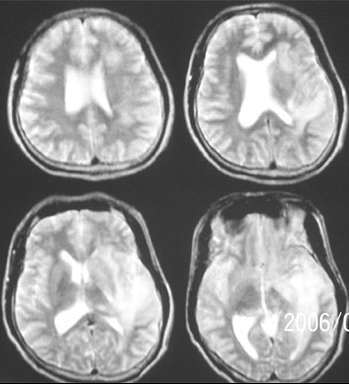

mr是增强

左侧基底节额颞叶稍长t1长t2信号,增强见边缘与脑回样强化,作侧脑室变窄。ct平扫呈等与扫地密度以等密度为主。考虑1脑炎。2脑肿瘤[淋巴瘤]

ct示左颞叶等,略低密度影,mr示左额颞叶t1wi呈低信号,t2wi呈高信号,增强后边缘不均匀强化,左侧脑体部明显受压,考虑脑梗塞可能性大

首先考虑脑梗塞,肿瘤mri表现多为长t2信号,增强后多有明显的不均匀强化,本病例占位征象明显,如果是肿瘤恶性度是偏高的,增强后应该有明显的强化表现。临床病史比较短暂,增强后强化呈条片状,梗塞在三天为水肿高峰,占位明显。综合考虑脑梗塞可能性大。

mr 片与ct 吻合不起来。ct上双侧额叶大片低密度影像,而mr上额叶却没有异常信号。是不是两个检查相隔时间较长?或者ct 扫描时头颅不在机架中心而偏下出现的伪影?如果不是伪影怎么没有一点占位效应?